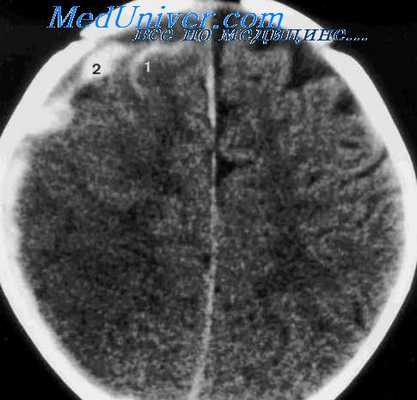

(а) Бесконтрастная КТ: у пожилого пациента с множественными падениями в анамнезе определяется разделенное на полости скопление «пенящейся» жидкости. Отмечаются многочисленные границы раздела кровь - жидкость.

(б) КТ-ангиография: у этого же пациента определяется скопление «пенящейся» жидкости в форме полумесяца. Обратите внимание на смещение кнутри головного мозга, а также компрессию борозд и смещение корковых вен.